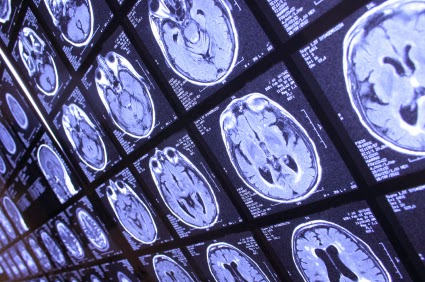

How do we know a patient is brain dead? I did a three-part series on this very issue that you can read here, here and here. These tests were done on Jahi and it was determined by multiple medical experts that she’d suffered whole brain death– so not even her brainstem had bloodflow. Whole brain death is considered legal death. It cannot be reversed.

Think of what the brain controls— everything. It is the computer hard drive of your body. If it has died– it is no longer signaling the production of hormones that control vital body functions. If the brain isn’t doing this– then we as medical providers have to administer medications that will do this. Because of this, the whole body begins to decompose and the heart will eventually stop beating.